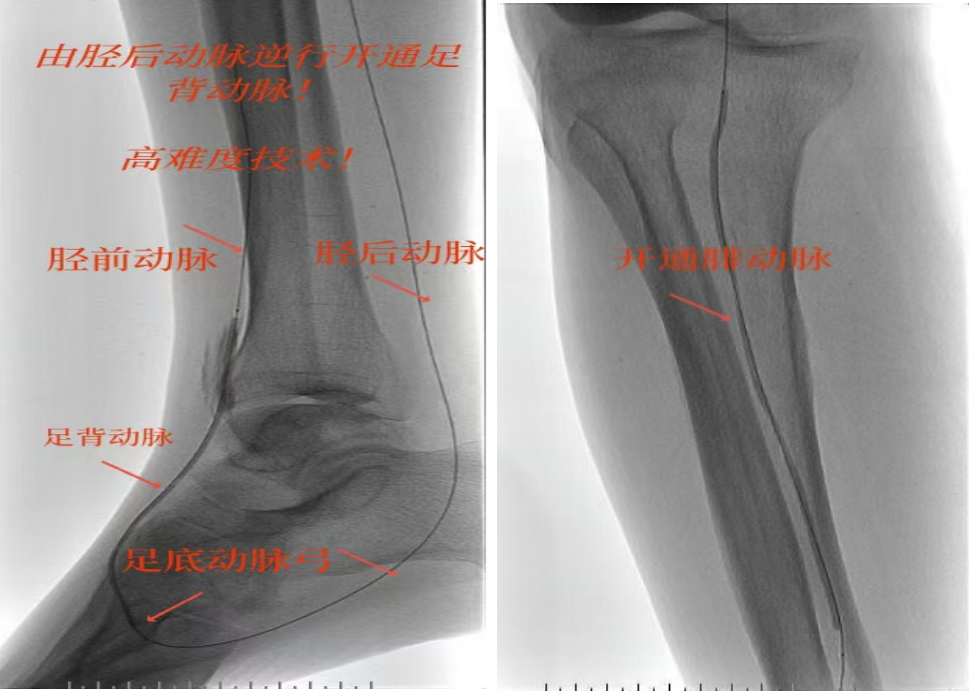

绝处逢生!“糖足”患者免截肢|市中医医院高难度介入“逆行破冰”立大功!